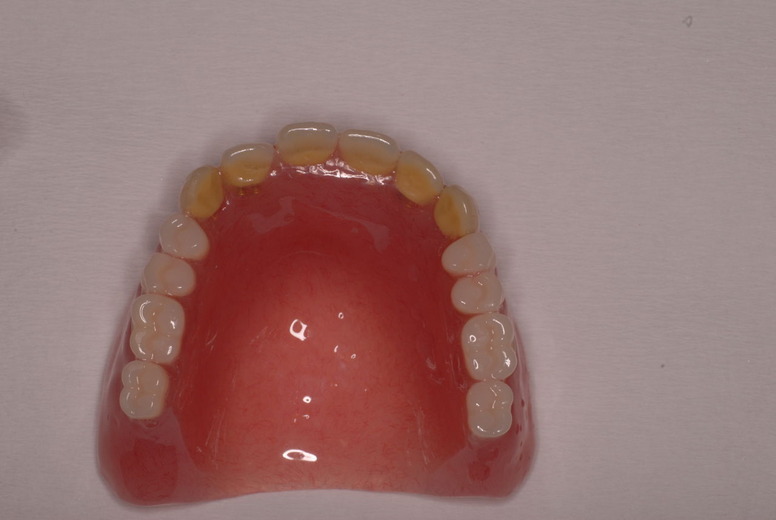

外注で完成させた入れ歯です。

違いは歯の位置です。あまりに外側で噛むと動くから噛めないのです。